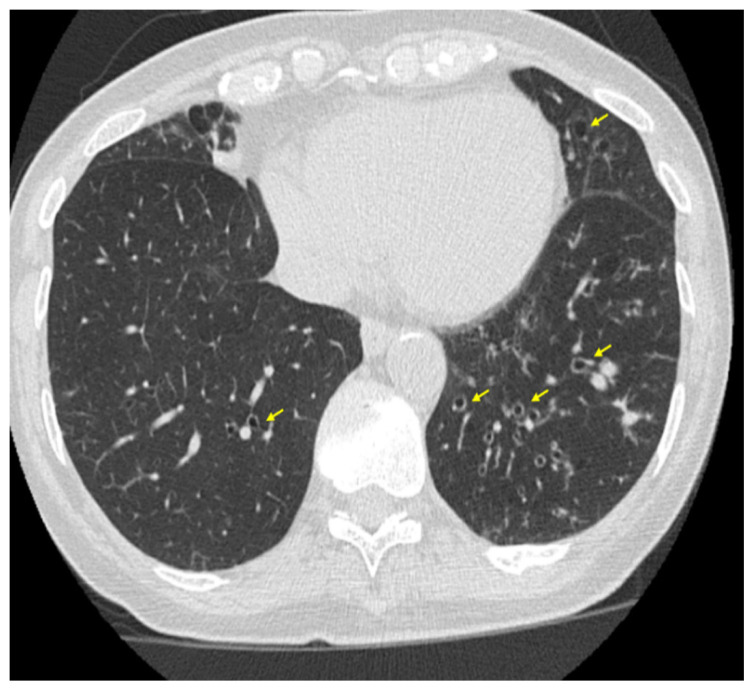

Premature Ventricular Contractions as an Underrecognized Cause of Chronic Cough: A Case of Misdiagnosis in a Patient with Bronchiectasis.